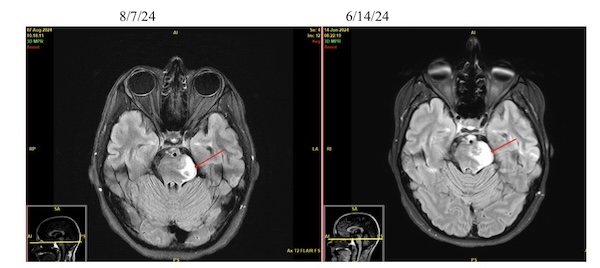

In August of 2022, I completed 30 rounds of proton beam radiation therapy down in Rochester, and that went smoothly, and after that, my check-ups went every two months to every three months to every six months. In 2023, I graduated with my first bachelor’s degree. And then on June 14, 2024, I got the news that no one wants to hear, “Your tumor is progressing rapidly, and we want you start chemotherapy asap.”

I was supposed to complete six rounds of the TMZ, but it seemed like at every check up nothing good would ever come up and I was beginning to become weaker, more tired, and many other things by December 2024. My platelets were down to like 15, and they were going to do a blood transfusion, but when they checked again, my platelets had already jumped to 20, so they wanted to wait another day to see if they jumped anymore. After that whole mess, they switched me to a medication called Avastin, which is an infusion every three weeks, and has brought me the best results I could’ve asked for. Flair spots have decreased, blood supply to the tumor has decreased, and I am currently still on Avastin. It’s difficult because they still aren’t sure how long they want me to have these infusions.